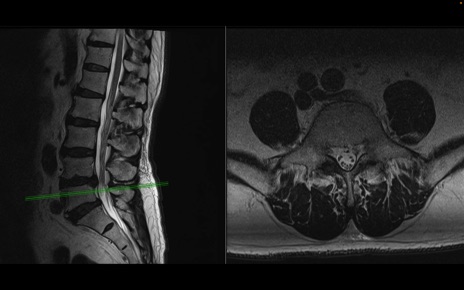

【整形】TIPS症例2 腰椎MRI 横断像と矢状断像

【症例】70歳代男性

【主訴】左下肢痛

【現病歴】2週間前くらいから腰痛、左下肢痛あり。左臀部から大腿、下腿外側のしびれが常時ある。歩行とともに同部位の痛みあり。

【身体所見】Lasegue70-/60+、Bragard-/±、PTR ±/±、ATR -/-、IP 5/5、TA 5/4、TS 5/5、EHL 右第1足趾なし/3、FHL 5/5、hypersthesia(-)、足背動脈触知良好

異常所見と診断は?